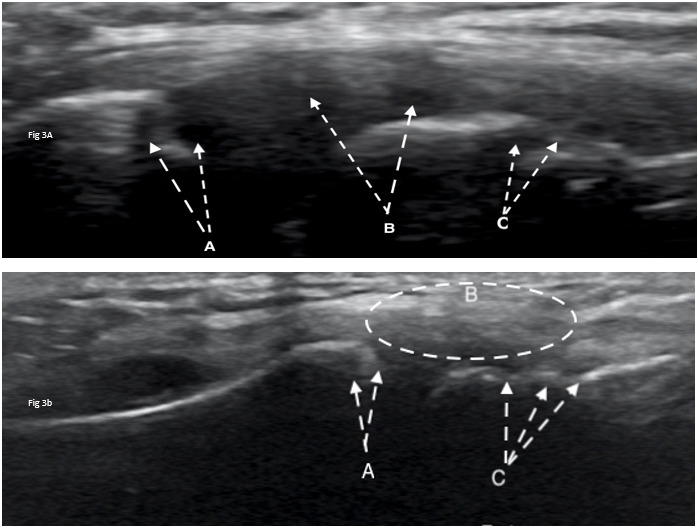

Diagnostic ultrasound imaging (GE Logiq E9; 2010) of the biceps tendons, tendons of the rotator cuff, rotator interval, labrum and anterior/posterior ACJ was performed immediately following the physical examination. Ultrasound confirmed misalignment of ACJ (clavicular portion elevated) with distinct hypoechoic patterns noted on both the clavicular and acromial attachments of the capsule, with associated bony abnormalities (Figure 3A, 4A). Further, a small supraspinatus myotendinous partial thickness tear was also identified. The labrum was not adequately visualized with the ultrasound study.

At the one-year follow-up, the subject reported no pain (NPRS=0/10) and full return to athletics (QDASH =0% disability). A follow-up MRI at one year revealed no discrete labral tears, minimal supraspinatus tendinopathy, and normal visualization of the ACJ (Figure 5B). Similarly, a one-year follow-up diagnostic ultrasound revealed normal appearance of the supraspinatus tendon, its myotendinous junction and ACJ (Figure 3B, 4B).